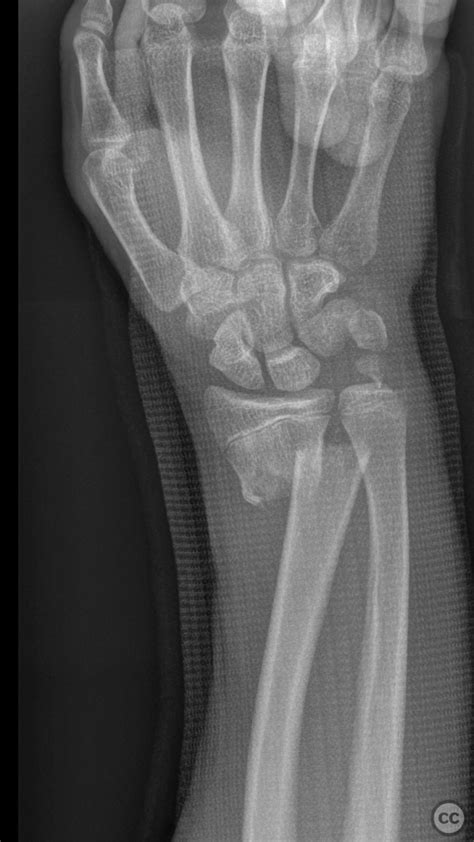

Before we jump into the specifics of the Kapandji technique, let’s quickly cover what a distal radius fracture actually is . Essentially, it’s a break in the radius bone, near the wrist. Distal radius fractures are incredibly common, especially among older adults with osteoporosis and individuals who participate in high-impact sports. These fractures often occur when you try to break a fall with an outstretched hand. The severity of a distal radius fracture can vary widely, from a small crack to a complete break with multiple fragments. Symptoms typically include immediate pain, swelling, bruising, and difficulty moving the wrist. Sometimes, the wrist may appear deformed. Diagnosis usually involves a physical examination and X-rays to determine the extent and type of fracture. Depending on the severity, treatment options can range from non-surgical methods like casting or splinting to surgical interventions. Understanding the nature of the fracture is crucial in determining the best course of action. We need to know if the bone is simply cracked, broken into pieces, or displaced. All these factors influence whether the Kapandji technique is a suitable option.